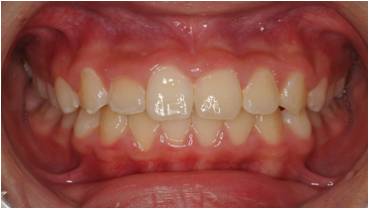

治療後

乱ぐい歯の小児矯正治療(10歳の女子)の治療前後の写真です。矯正治療によって前歯の強い叢生(ガタガタ)・ねじれが大幅に改善され、咬合関係も良好になりました。

| リスク・注意点 | ・後戻り防止のための保定装置使用とブラッシングの継続が重要 |